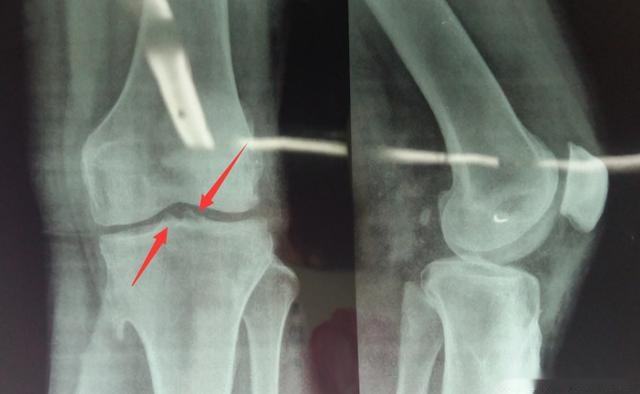

X线平片不仅为骨质增生的常规检查方法,有的学者还认为骨质增生的X线检查是追踪病情变化的金标准。

骨刺的X线片可分为五级:

0级:无改变;

1级:轻微骨赘;

2级:明显骨赘,关节间隙正常;

3级:骨赘外关节间隙中度狭窄;

4级:骨赘外关节间隙严重狭窄,伴软骨下骨硬化。